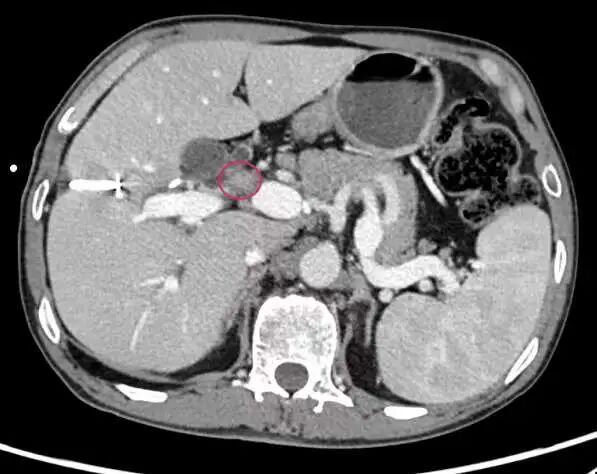

近日,四川大学华西医院胆道外科程南生、李富宇教授团队为一例胆囊癌累及血管、胆管的患者,成功实施了包含肝切除术、胆管分叉切除、门静脉切除重建、肝右动脉修补、扩大淋巴结清扫、多支胆管吻合在内的腹腔镜胆囊癌扩大根治术。 经文献检索,国内外未见胆囊癌患者在腹腔镜下实施包含门静脉切除重建在内的胆囊癌扩大根治术的相关报道。 老赵(化名)平时在工地上打零工,3个月前,老赵觉得上腹胃这个部位开始不舒服,连忙去卫生院检查,被告知没得胃病是胆囊结石,开了点消炎利胆的药吃了几天就感觉好点了。 但是一个月过会,老赵的眼睛、全身皮肤逐渐开始发黄,皮肤瘙痒,上腹部又感觉隐痛不适,吃饭后腹胀,大小便颜色都不正常了,小便就像浓茶、大便就像陶土。老赵以为自己发了肝炎或者什么传染病,赶紧到当地人民医院看病,CT、MRI等等检查都做了,最后被婉转地告知得了胆囊癌。 家人四处打听,老赵辗转了多家医院后来到华西医院胆道外科程南生、李富宇教授团队处就诊。 胆囊位于右上腹肋骨下,主要作用是贮存肝脏分泌的胆汁,也就是所谓的“苦胆”,当进食时诱发胆囊收缩,胆汁排入肠道帮助消化食物,“让我们吃饭更香”。 胆囊癌是消化系统第五大恶性肿瘤,是胆道系统最常见的恶性肿瘤。早期胆囊癌临床症状不明显,仅有右上腹部不适、疼痛等类似胆囊结石症状,肿瘤侵犯胆管后眼睛和皮肤会变黄,肝功严重受损,如不及时诊治,会导致肝功衰竭危及生命。 发病率“高” 近年来,世界范围内胆道肿瘤的发病率逐渐增加,我国的胆囊结石患病率已与欧美接近,胆囊癌发病率也随之增加。 发现“难” 胆囊癌起病隐匿,临床症状不明显,早期多数患者没有临床症状,仅有右上腹部不适、疼痛等类似胆囊结石症状。多数胆囊癌患者在诊断时已属进展期或晚期,部分病例丧失手术机会,如何提高进展期胆囊癌的切除率至今仍是胆道外科中的难点与重点。 根治“难” 此外,胆囊癌切除率低和预后较差的另一个重要原因在于肿瘤侵袭性强,容易发生毗邻脏器和血管的侵犯。胆囊颈部和胆管的后方就是门静脉和右肝动脉,进展期胆囊癌极易侵犯临近的胆管、肝动脉、门静脉、胃窦、结肠、胰头等部位,该部分病例需进行包含联合脏器切除或血管切除的扩大切除才能获得根治性切除,手术难度大、切除率较低。 然而,包含血管切除重建在内的根治术目前仍是胆囊癌患者获得长期生存的主要治疗手段。 老赵的胆囊癌已经累及血管、胆管,术前眼睛和皮肤发黄,食欲体重下降明显。胆囊癌对药物治疗不敏感,如不实行手术,他的生存期一般仅半年至一年。综合考虑过后,程南生、李富宇教授团队决定为老赵行腹腔镜胆囊癌扩大根治术。 术前CT显示肿瘤位置 由于老赵存在胆管梗阻,术前手术团队为他先做了胆道穿刺引流改善肝功至正常,合并营养改善后才正式实施手术。 术中见肿瘤不仅侵犯和阻塞肝脏胆汁分泌的主要流出道-胆管,更糟糕的是还多处侵犯了肝脏血液供应的主要流入道—门静脉主干、门静脉右支起始部,并致密包饶了肝脏血液供应的另一主要血管—肝右动脉。 如果不能切除肿瘤受累的血管并成功重建肝脏的主要供血血管-门静脉,只能放弃根治性切除手术,老赵的生存期将会很短。 对此,手术团队在腹腔镜下分别分离出和阻断门静脉左支、右支和主干,切除门静脉受累部分,在肝门狭窄的空间内成功完成腹腔镜下门静脉重建。 肿瘤在侵犯胆管、门静脉的同时,360度致密包饶肝右动脉。 虽然老赵的胆管梗阻经过术前胆道穿刺引流改善肝功,但胆汁性肝硬化严重,无法耐受扩大右半肝切除,而肝右动脉如无法在腹腔镜下从肿瘤中剥离出来只能放弃根治术。 团队在术中经腹腔镜下仔细解剖分离,采用打开肝动脉血管外鞘膜技术,发现肝右动脉并未受侵犯,将肝右动脉从肿瘤包饶中艰难剥离出来,在腹腔镜下修补多处肝动脉破口。 腹腔镜下切除肝门部胆管分叉后,再进行多支细小胆管断端的胆肠吻合。 由于解剖关系或肿瘤侵犯,胆道肿瘤多数需要附加大范围的肝切除、规范的淋巴结清扫、精准的胆肠吻合术、血管切除重建或联合脏器切除,因而手术更为复杂和耗时。 目前国内外常规开展胆囊癌腹腔镜根治术的单位极少,未见胆囊癌患者在腹腔镜下行门静脉切除重建、肝动脉修补的相关扩大根治术文献报道。我院胆道外科程南生、李富宇教授团队在前期胆囊癌腹腔镜联合脏器切除和再次手术根治的经验基础上,完成了该例包含血管切除重建在内的腹腔镜胆囊癌扩大根治术。 术中严格遵循无瘤原则,腹腔镜血管切除重建达到了开腹手术的解剖标准,在保障患者远期疗效的前提下,术后运用加速康复外科理念,老赵术后恢复速度明显快于传统开腹手术。 出院的时候,老赵说,“我无法用言语来表达我的谢意和敬意,医生护士们说我听话好好康复、好好生活就是对他们最大的表扬!” 腹腔镜根治性术已经广泛应用在胃肠、肝脏和胰腺肿瘤,并且成为了常规术式之一,但腹腔镜胆道肿瘤目前在世界范围内均刚起步。特别是像腹腔镜胆囊癌根治术这种复杂耗时的手术,国内外开展的单位极少,但技术的进步和发展趋势是必然和必须的,也是外科医生的追求和职责所在。 胆道外科程南生、李富宇教授团队从2015年开始率先探讨腹腔镜胆囊癌根治术,初期无经验可借鉴,在华西“精业、创新”文化底蕴的支撑下,聚焦胆道肿瘤的微创外科的发展方向,严格遵循国际指南和当前技术难点,制定并实施了一系列规范化的诊治和手术流程、不断优化手术步骤与改进技术,进展期胆囊癌的切除率和微创完成比例明显提升。 目前团队完成的胆囊癌再次腹腔镜根治术例数、T3期胆囊癌腔镜扩大根治术例数均系国际单中心例数最多的团队之一;完成的胆道探查术后、联合多脏器切除的腹腔镜胆囊癌再次扩大根治在国际上均未见相关报道。他们的系列探索有助于改变目前进展期胆囊癌无法在腹腔镜下完成联合脏器和血管切除的传统观念,有助于改善目前国际上胆道肿瘤微创化起步晚、进展缓慢和微创手术适应症窄的局面。 精业、创新,华西人永远在路上!